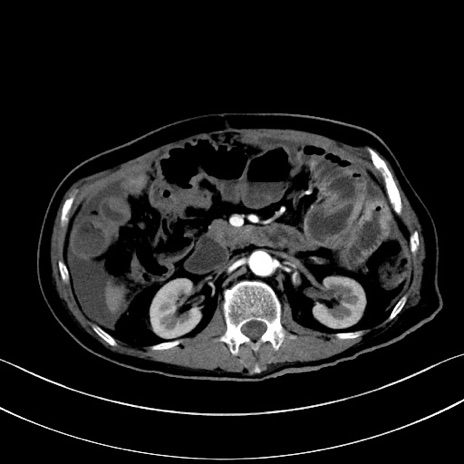

症例28(横断像)

【症例】60歳代男性

【主訴】嘔吐

【現病歴】胃癌にて胃全摘後。食思不振が悪化し、夜中に嘔吐することがある。

【既往歴】胃癌、胃全摘、脾摘、胆摘後

【データ】WBC 5900、CRP 10.56